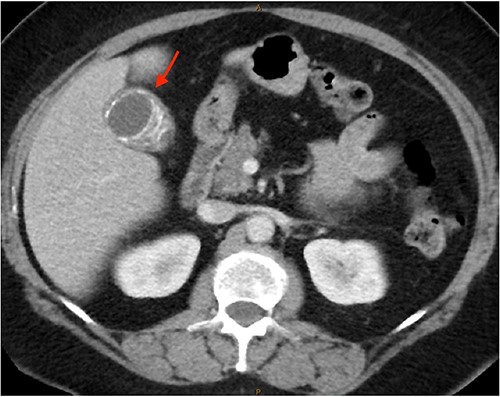

As only part of her gallbladder was imaged on the non-contrast CT lumbar spine, a repeat CT scan of her abdomen and pelvis with portal venous contrast was ordered. This showed semi-annular wall calcification at the gallbladder body suggestive for porcelain gallbladder and several calcified gallstones with largest measuring up to 32 mm (Figs 1–3). No gallbladder soft tissue mass was seen.

Semi-annular wall calcification at the gallbladder body—axial view.